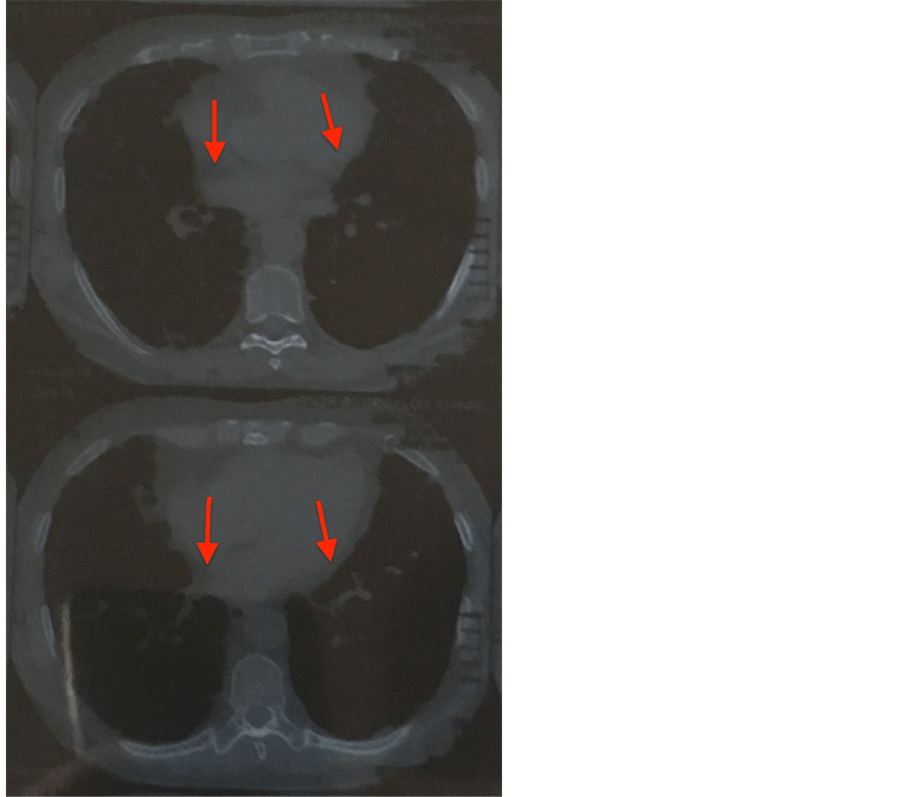

From www.researchgate.net

Chest Xray before discharge and after nitrofurantoin withdrawal Chest Pain After Taking Nitrofurantoin Headache* constipation* * to learn more about this side effect, see the “nitrofurantoin’s side effects explained” section. Symptoms of acute pulmonary reactions usually include fever, chills, cough, chest pain, dyspnoea, pulmonary infiltration with. The inflammation is usually accompanied by high. Difficulty breathing, fever, chills, chest pain and cough. You get pins and needles, tingling. Serious skin rash that looks red,. Chest Pain After Taking Nitrofurantoin.

From www.scirp.org

Pulmonary Fibrosis Due to Nitrofurantoin Therapy A Case Report Chest Pain After Taking Nitrofurantoin Symptoms of lung inflammation can include tiredness, fever, chills, cough, chest pain, and shortness of breath. Serious skin rash that looks red, swollen, blistered or peeling. Headache* constipation* * to learn more about this side effect, see the “nitrofurantoin’s side effects explained” section. Difficulty breathing, fever, chills, chest pain and cough. Symptoms of acute pulmonary reactions usually include fever, chills,. Chest Pain After Taking Nitrofurantoin.

Pulmonary Fibrosis Due to Nitrofurantoin Therapy A Case Report Chest Pain After Taking Nitrofurantoin Symptoms of acute pulmonary reactions usually include fever, chills, cough, chest pain, dyspnoea, pulmonary infiltration with. You get pins and needles, tingling. If you have any of these symptoms, contact your doctor right away. Headache* constipation* * to learn more about this side effect, see the “nitrofurantoin’s side effects explained” section. Difficulty breathing, fever, chills, chest pain and cough. Symptoms. Chest Pain After Taking Nitrofurantoin.

Chest Xray before discharge and after nitrofurantoin withdrawal Chest Pain After Taking Nitrofurantoin This rare possible side effect can occur after taking the medication for a very long time (over 6 months). Symptoms of lung inflammation can include tiredness, fever, chills, cough, chest pain, and shortness of breath. Difficulty breathing, fever, chills, chest pain and cough. Call 999 or go to a&e if: You get pins and needles, tingling. Headache* constipation* * to. Chest Pain After Taking Nitrofurantoin.